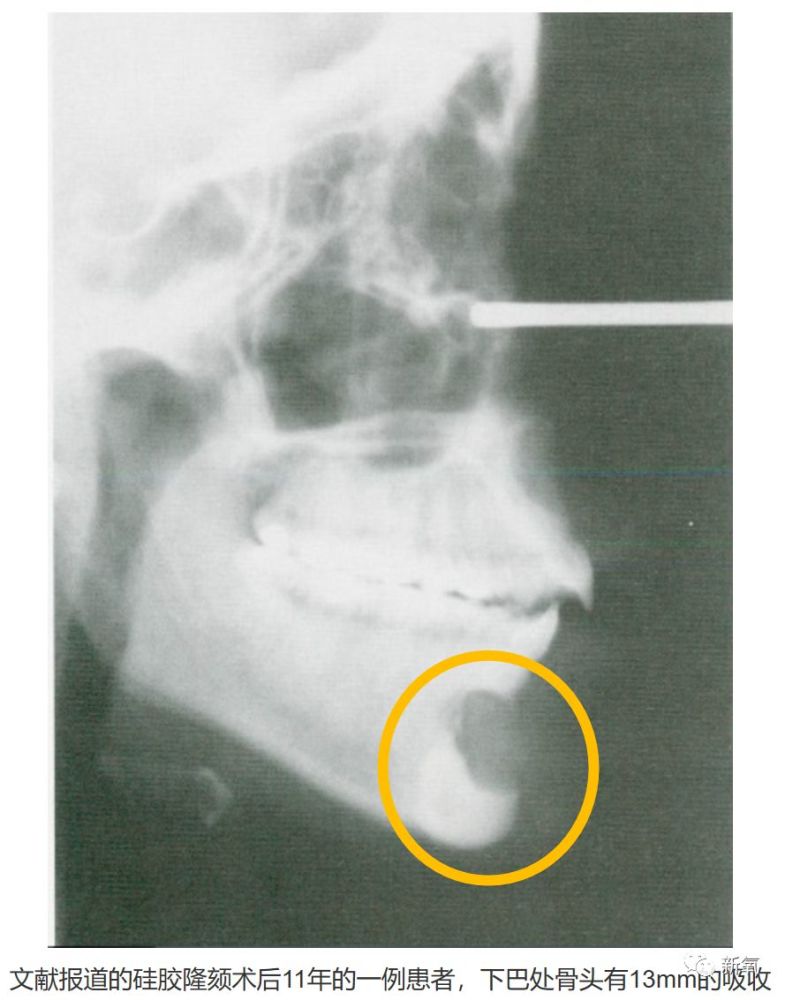

骨吸收有可能让一个人的神仙鼻变成巫婆鼻?